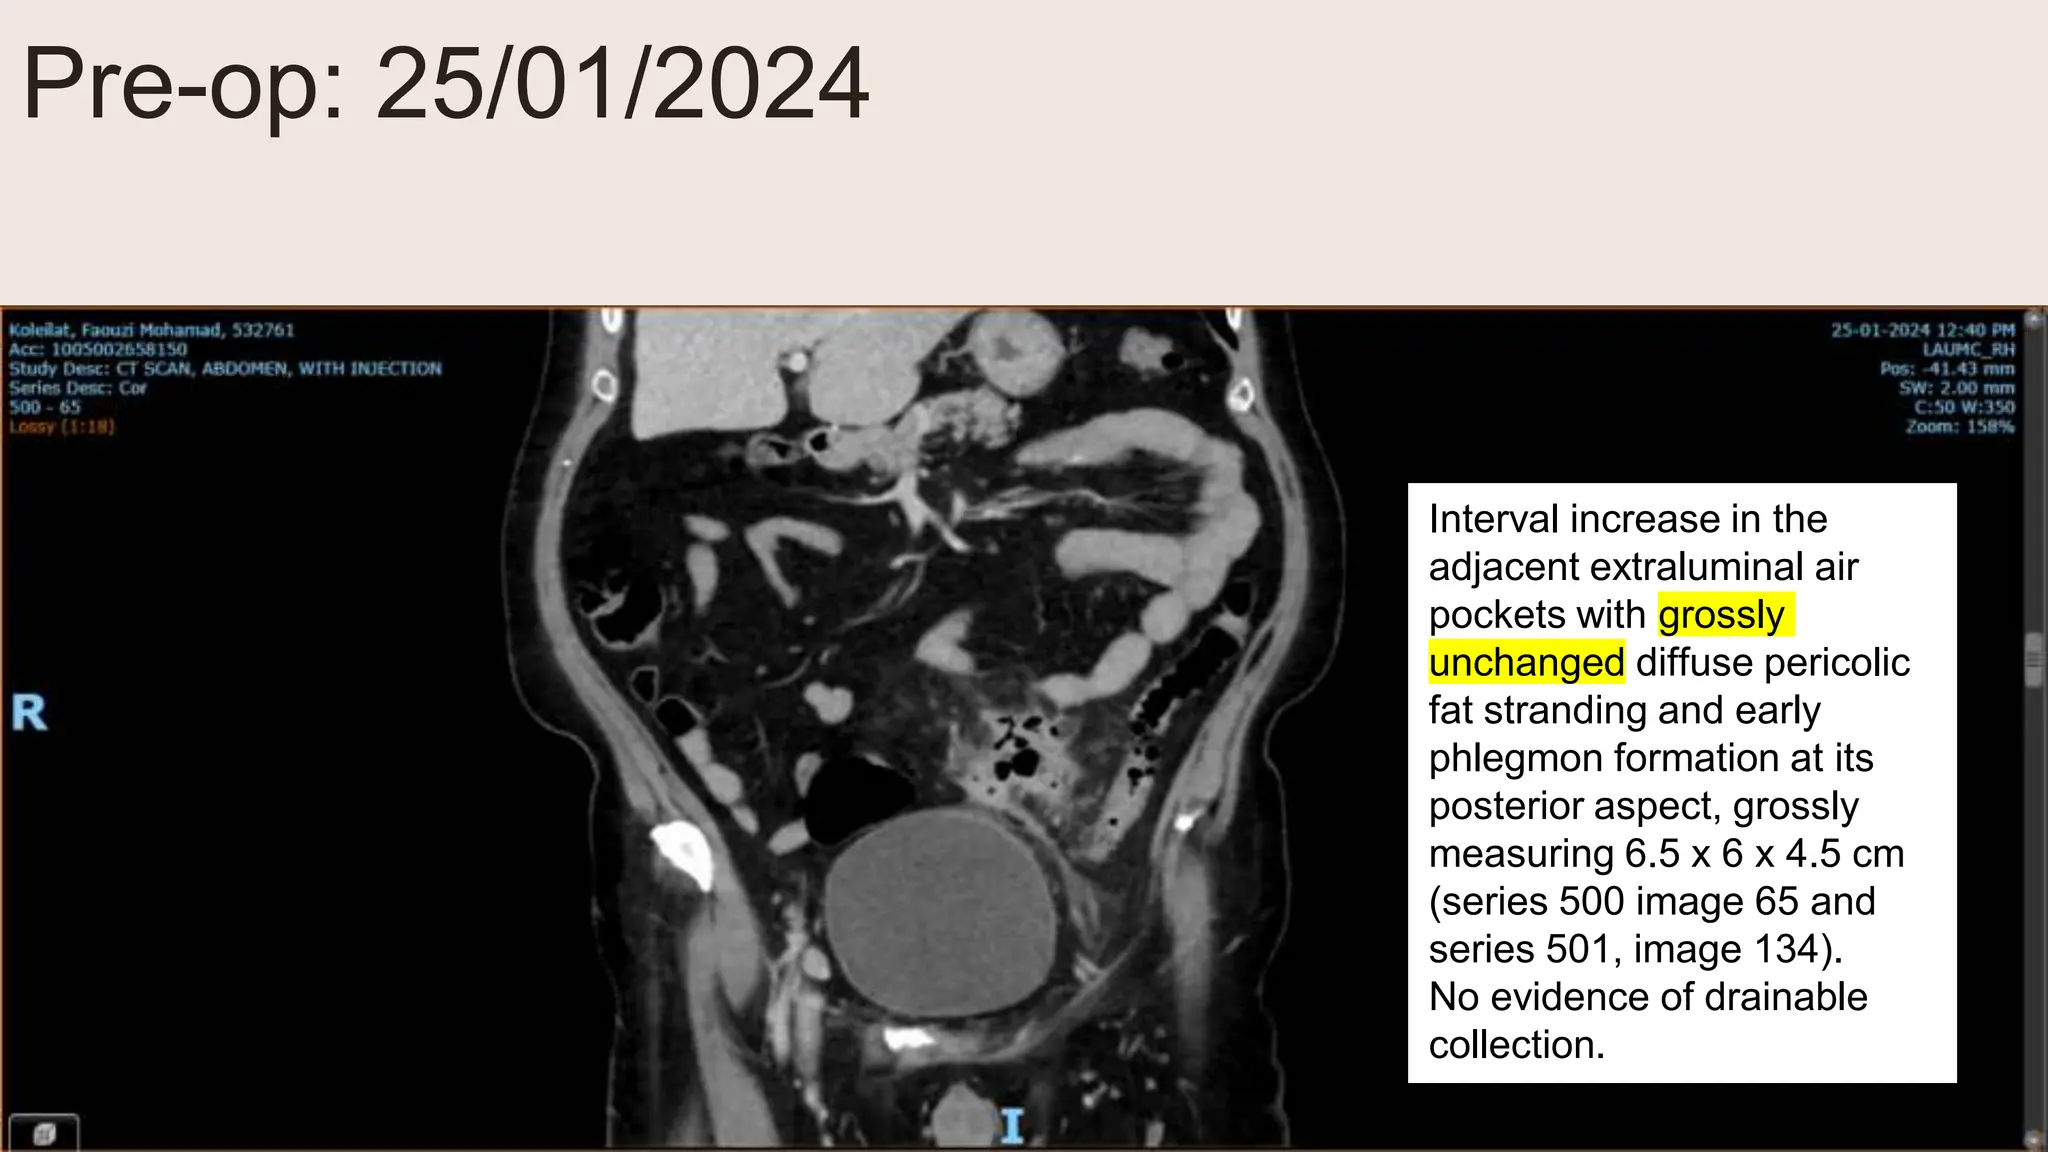

Pre-op: 25/01/2024

Interval increase in the

adjacent extraluminal air

pockets with grossly

unchanged diffuse pericolic

fat stranding and early

phlegmon formation at its

posterior aspect, grossly

measuring 6.5 x 6 x 4.5 cm

(series 500 image 65 and

series 501, image 134).

No evidence of drainable

collection.